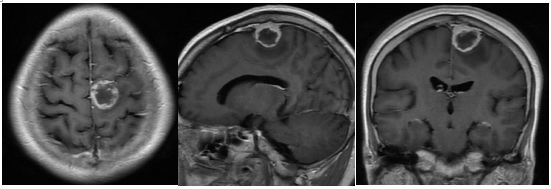

排除手术禁忌后,于05-29在全麻下行“左顶部肿瘤切除术”。术中见肿瘤位于左侧顶部矢状窦旁,与脑膜粘连紧密,血供中等,质地较韧,呈实质性。取少量肿瘤组织送冰冻提示(左顶部矢状窦旁)脑膜瘤。肿瘤予显微镜下全切(图2)。

图2. 术中所见

图3. 术后复查头颅磁共振,示肿瘤全切。

术后患者神志清,对答切题;复查MRI示肿瘤全切。至术后一周出院时右下肢肢体肌力4+级,活动可以控制,余无阳性体征发现。